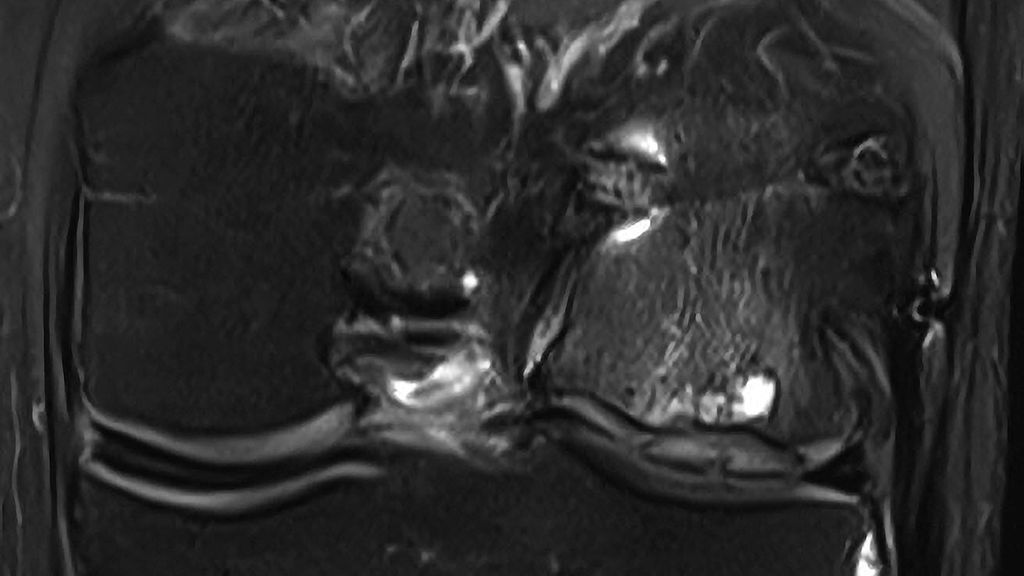

Abb. 1: Hypertrophie des Knorpelregeneratgewebes am lateralen Femurcondylus nach MACT (matrixgekoppelte autologe Knorpeltransplantation) mit subchondraler Zystenbildung

Abb. 2: Das arthroskopische Korrelat des MRT-Bildes zeigt ein instabiles Knorpelregenerat mit fehlender Integration und beginnender Delamination